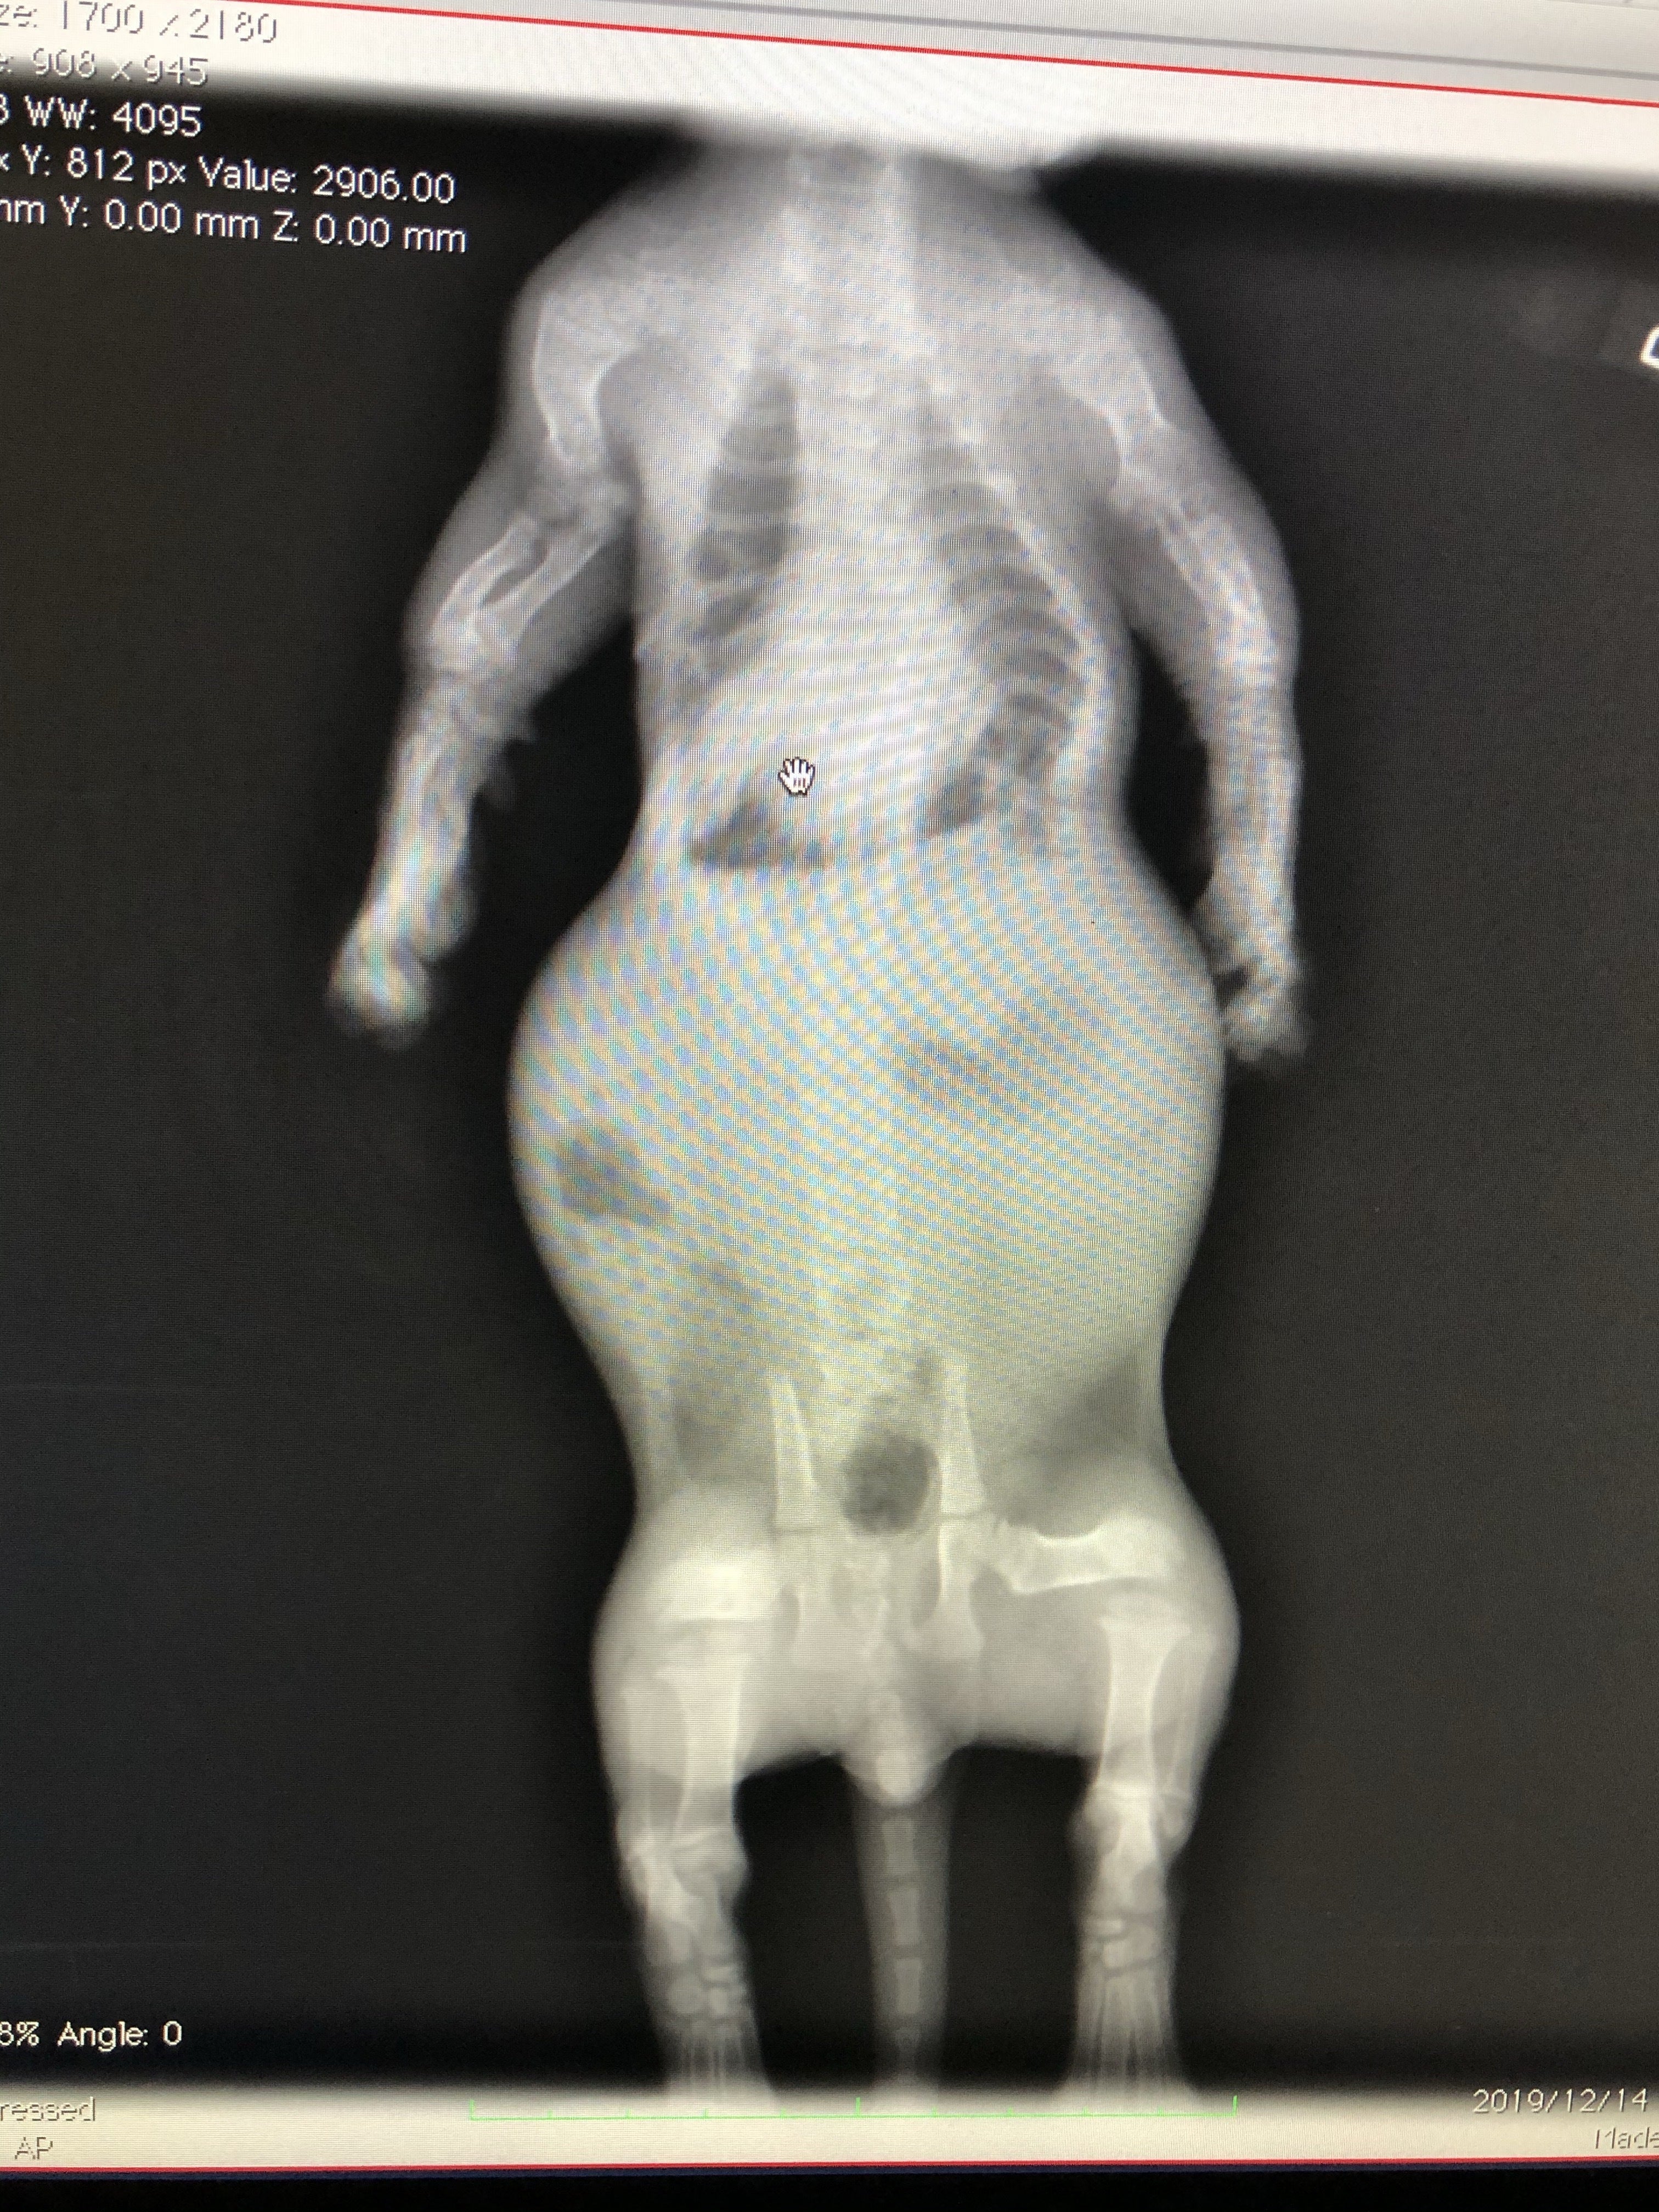

肋骨変形に伴う脊椎側変症

先天的な骨格異常で背骨と肋骨が変形していると診断されました。

また、この骨格異常により、肋骨と背骨の間のスペースが狭く、このまま成長していくと心臓と肺が圧迫され最悪生きられないと言われました。

よく休憩していたのは肺のスペースが狭いことによる影響で呼吸がしにくかったようです。